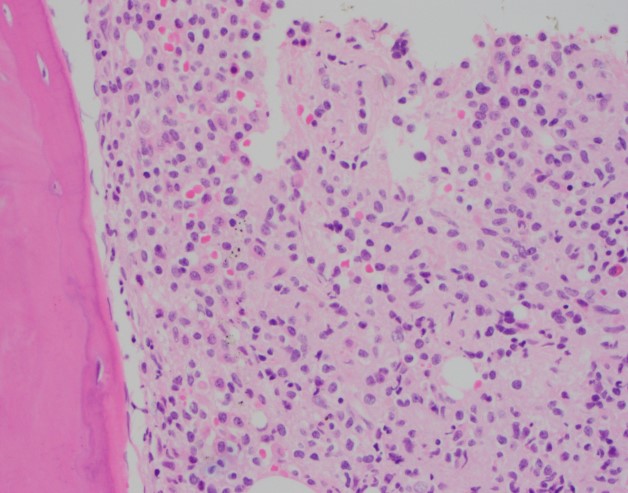

Review of the peripheral blood confirmed a markedly pancytopenic picture with virtually no leukocytes in the region of best RBC “spread” (Image 1A). In the periphery of the smear (1B and C) clusters of leukocytes were noted where left-shifted granulocytes were seen. Many demonstrated nuclear irregularity and abnormal granulation (B) and some showed the presence of numerous Auer rods (Image 1C, arrows).

The presence of abnormally granulated immature neutrophilic precursors, and cells with numerous Auer rods was morphologically compatible with acute promyelocytic leukemia (APL) and a rush preliminary diagnosis was rendered. The patient was started on ATRA therapy and FISH for PML-RARA was expedited.

Two distinct subtypes of APL exist: hypergranular (typical) or microgranular. The hypergranular variant is filled with large Auer rods and with dense cytoplasmic granules that can obstruct the nucleus. In contrast, the microgranular variant has a scantiness of cytoplasmic granules or small azurophilic granules.

The immunophenotype for APL is quite distinct and characterized by low or absent expression of CD34 and HLA-DR (in keeping with the cellular differentiation from blast to promyelocyte). APL cells are positive CD33 and CD13 with most cases showing expression of CD117 (sometimes weak). APL cells are usually negative for CD15, CD65, CD11a, CD11b, and CD18. The microgranular variant may display positive staining for CD34 and CD2. For both variants, IHC with antibodies to the PML gene demonstrates a nuclear multi granular pattern with nucleolar exclusion, a finding that is unique to APL and not seen in AML or normal promyelocyte morphology.